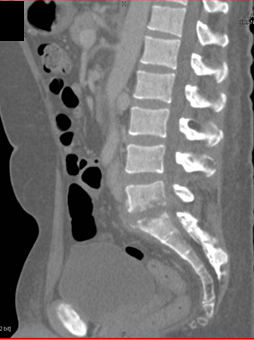

The best diagnosis in patient with left hip pain is?

sacral fracture

psoas bleed

osteomyelitis at L5-S1

metastases to L5 and S1